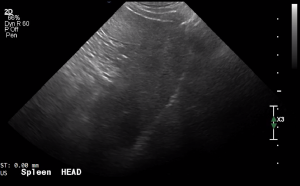

SIMON Ultrasound Database

This ultrasound database is a free resource for students and doctors!

Our collection includes videos of dogs, cats, horses, cows, humans, and many other species!